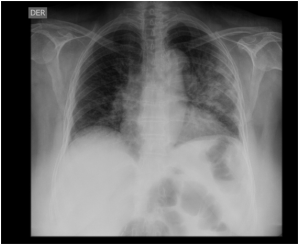

Se solicita la siguiente radiografía:

La radiografía fue informada como opacidades de relleno alveolar bilateral, de predominio izquierdo.

El patrón difuso, asociado a hiponatremia y la molestia gastrointestinal hacen sospecha de legionella como agente etiológico.